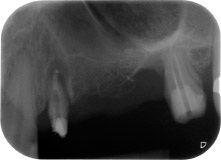

Une patiente de 58 ans se plaignait de douleurs et d'une mobilité accrue de la dent pilier 24 de son bridge. Présence d'une inflammation parodontale avec formation de poches de 7 mm de profondeur dans le sens mésiobuccal et de plus de 12 mm dans le sens distal, ainsi que d'une atteinte de la furcation au troisième degré. La radiographie a par ailleurs révélé une lésion parodontale étendue autour de la région apicale de la dent 24 ayant préalablement reçu un traitement endodontique (alio loco) (Fig. 1).

Un an plus tôt, les dents 25 et 26 avaient été extraites à la suite d'un traumatisme et pour cause d'atteinte endo-parodontale, avant la pose du bridge. Une lésion endo-parodontale combinée a été diagnostiquée pour la dent 24, d'étiologie incertaine. La patiente voulait conserver ses dents piliers 24 et 27 et refusait toute prothèse amovible à titre définitif, et même provisoire. Par conséquent, malgré un pronostic défavorable compte tenu des résultats des radios et des examens cliniques, il a été convenu de faire le maximum pour conserver les deux dents.